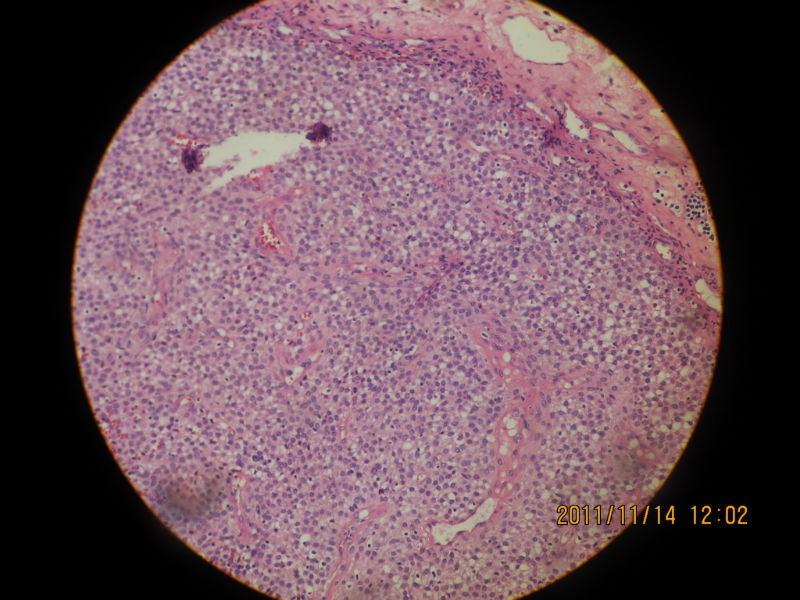

女性 65岁 鼻腔肿物

图1

图2

图3

图4

图5

图6

图7

图8

图9

图10